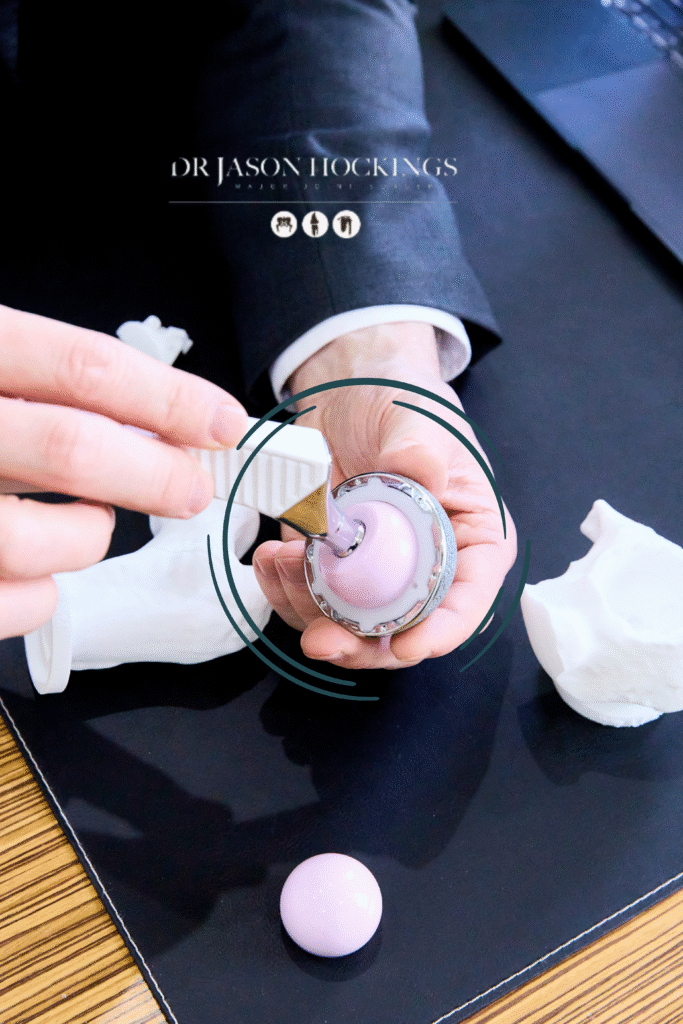

A total hip replacement is made up of three main prosthetic components:

ACETABULAR COMPONENT

The acetabular component replaces the socket of your hip joint. It usually consists of a titanium shell that fits securely into the pelvis, with a smooth inner liner made from either ceramic or highly cross-linked polyethylene to allow smooth movement of the joint.

ARTICULAR INTERFACE

The articular interface is the contact point between the femoral head (ball) and the liner within the socket. This surface allows the components to glide smoothly against each other, playing an essential role in joint movement, comfort, and the long-term performance of your hip replacement.

In most total hip replacement procedures, Dr Hockings uses the AMIStem-P Collared Femoral Component, designed to support bone preservation and long-term stability, together with the M-Pact Acetabular Cup system, which provides strong fixation and accommodates individual anatomical variation. These implants are developed by Medacta International, a Swiss orthopaedic company recognised for its evidence based approach to joint replacement innovation. While Dr Hockings frequently uses this combination, he carefully assesses each patient’s anatomy, bone quality, and surgical goals to determine the most appropriate implant configuration.

Inserting the acetabular cup: Once everything is confirmed, the final cup is inserted into the socket. A liner is then placed inside the cup to create the low-friction surface that allows your new hip to rotate, bend, and move comfortably.

Attaching the femoral head: A metal or ceramic head is attached to the top of the stem. This becomes the new ball of the joint and is placed into the previously inserted socket liner, completing the reconstructed ball-and-socket structure.